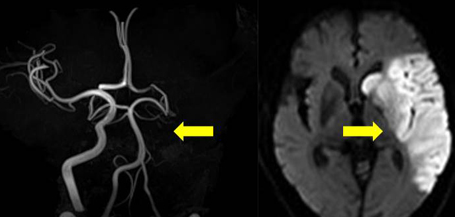

4. 진단 과정 및 필요한 검사

뇌경색이 의심될 경우 다음과 같은 검사를 통해 진단을 받을 수 있습니다: 정확한 진단은 적절한 뇌경색 치료방법을 선택하는 데 중요한 역할을 합니다.

- CT 스캔 : 뇌의 출혈 여부와 손상 정도를 확인할 수 있습니다.

- MRI : 뇌의 세부적인 구조를 검사합니다.

- 혈관 조영술 : 혈관 상태와 협착 여부를 파악할 수 있습니다.